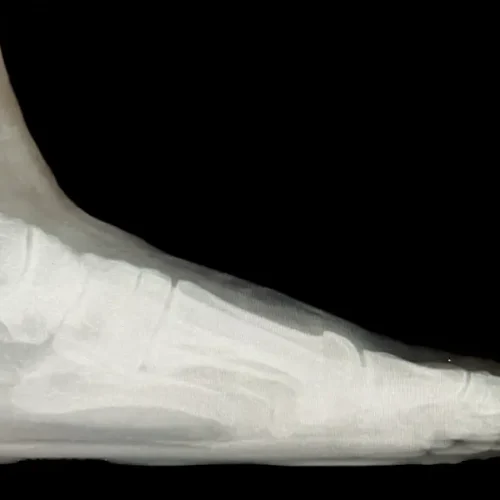

Surgical Intervention at Stepwell Institute is never a “one-size-fits-all” solution. We view surgery as a precise tool used to restore the natural biomechanics of the foot and ankle when non-invasive methods have reached their limit. Our philosophy centers on individualized surgical planning—using advanced imaging to map out the procedure before you ever enter the operating room. From correcting bunions and hammertoes to performing ligament repairs and fracture fixations, Dr. Yakov utilizes techniques designed to minimize trauma to the surrounding tissues, thereby reducing the risk of complications and ensuring a more stable, long-term result for our patients.

Stepwell Institute distinguishes itself by offering NJ patients access to the most advanced surgical modalities in modern podiatry. We specialize in Surgical Intervention, which utilize smaller incisions and specialized instruments to reduce post-operative pain and scarring. For more complex cases, we employ 3D-printed surgical guides and biological grafts to enhance the body’s natural healing ability. By choosing Stepwell Institute, you benefit from a specialized recovery plan where Dr. Yakov and our team prioritize early, safe mobilization. Our goal is to provide a definitive surgical solution that allows you to return to the active New Jersey lifestyle you love with confidence and strength. confidence and strength.

Our Case Study